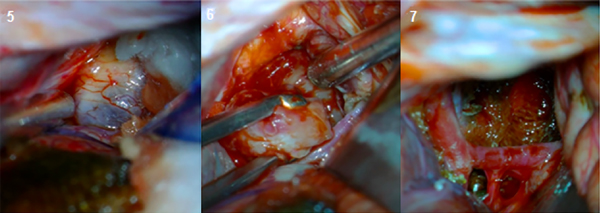

En el intraoperatorio se aprecia lesión con invasión del quiasma y nervios ópticos, de consistencia heterogénea, con componentes óseos en su interior (Figura 5-7).

Figura 5, 6, 7. Imágenes intra-cirugía.